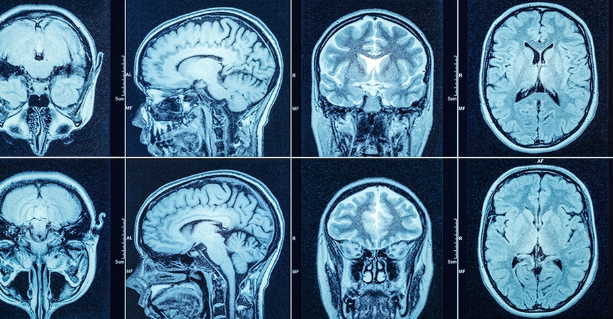

CT는 일반 촬영과 조영제를 활용한 촬영으로 나뉘며, 조영제를 사용하는 경우 비용이 상승합니다. 조영제는 혈관을 통해 뇌의 혈류 흐름 등을 더 정밀하게 확인하기 위해 사용됩니다.

일반 CT

보통 10~20분 내외로 촬영이 완료되며, 비교적 비용이 저렴합니다. 이 경우 촬영 자체만으로는 충분한 정보를 얻기 어려운 경우도 있으나, 초기 확인 목적에는 적합하다는 설명을 들었습니다.

조영제 CT

검사 전 조영제를 주사하며, 고해상도 촬영이 가능하지만 비용은 5만~10만 원 이상 추가됩니다. 조영제를 사용할 경우 사전 금식이 필요하거나 부작용 안내를 받기도 하므로, 절차가 조금 더 까다롭습니다.